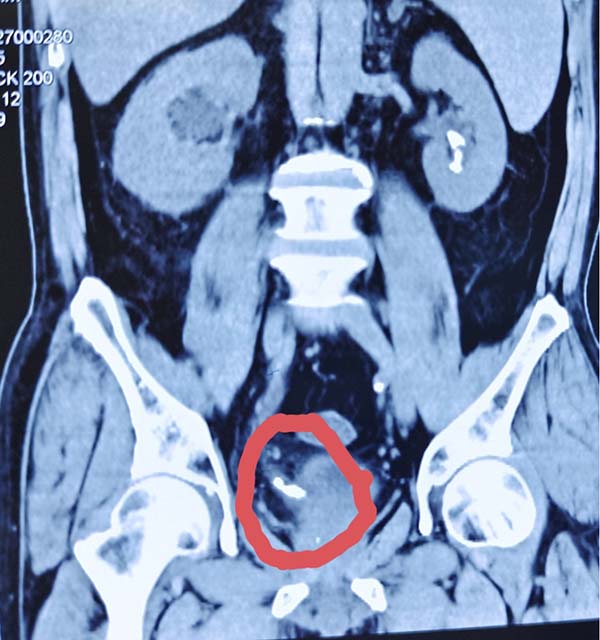

据悉,该患者因腰部剧烈疼痛并伴有血尿症状来院就诊。经检查,发现其输尿管上段嵌顿着2颗较大结石,下段1块结石。若采用传统单一的手术方式,往往需要分次进行,一次经尿道输尿管硬镜激光碎石术,一次经皮肾镜激光碎石术,不仅增加患者痛苦和经济负担,也延长了治疗周期。

手术当日,在于春虎主任的精准操作下,团队首先利用输尿管硬镜经尿道进入,顺利处理了位于输尿管下段的结石。随后,在硬镜建立的通道基础上,将纤细灵活的输尿管软镜送达位置更深、角度更刁钻的输尿管上段。软镜前端可弯曲的特性,使得医生能够无死角地观察结石情况,并利用先进的激光碎石设备将结石精准粉末化。最终,手术团队成功将输尿管上段和下段两处的结石一次性彻底清除。整个手术过程流畅,最大限度地减少了对患者正常组织的损伤。目前,该患者恢复良好,对手术效果非常满意,已经康复出院。